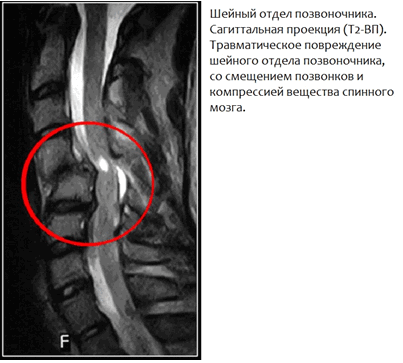

МР-томография позвоночного столба позволяет выявить следующую патологию: 1. Обнаружить дегенеративно-дистрофические повреждения межпозвонковых дисков (протрузия, грыжа) и тел позвонков; 2. Дисгормональные спондилопатии (поражение тел позвонков в результате выраженного нарушения гормонального фона); 3. Определить степень давления на корешки нервов поврежденного диска; 4. Диагностировать аномалии развития тел позвонков и спинного мозга; 5. Диагностировать опухоли костной и нервной ткани; 6. Выявить сужение спинномозгового канала; 7. Увидеть травматические повреждения тел позвонков, вещества и корешков спинного мозга. 8. Обнаружить метастазы злокачественных опухолей (легких, предстательной железы, молочной железы и т.д.); 9. Демиелинизирующие заболевания вещества и корешков спинного мозга (рассеянный склероз, синдром Гийена—Баре и другие миелопатии); 10. Выявить воспалительные заболевания тел позвонков (болезнь Бехтерева, спондилит, спондилодисцит и т.д.); 11. Обнаружение пораженных тел позвонков инфекционно-воспалительным процессом (остеомиелит, туберкулезный спондилит). 12. Обнаружение деструктивных (некротических) процессов в телах позвонков. 13. Выявление сосудистых аномалий (артерио-венозные мальформации) и участков c нарушением кровообращения вещества спинного мозга; 14. Планирование оперативного вмешательства на позвоночнике и/или спинном мозге и постоперационный контроль эффективности.

• деформирующий спондилез, остеохондроз шейного отдела позвоночника; • протрузии и грыжи межпозвонковых дисков шейного отдела позвоночника; • метастазы различных опухолей и первичное опухолевое поражение позвонков шейного отдела позвоночника; • стеноз позвоночного канала различной этиологии; • травмы шейного отдела позвоночника (перелом, вывих, подвывих, смещение тел позвонков); • различные аномалии развития тел позвонков (бабочковидный позвонок, синдром Клиппеля-Фейля и др.); • наличие различных патологических изменений в шейном отделе спинного мозга; • шейная миелопатия; • шейная радикулопатия; • копрессионные изменения в шейном отделе или его травматические повреждения; • воспалительное повреждения позвоночника; • подозрение на опухоль; • диагностика аномалии Киари и полостей (сирингов) в спинном мозге (необходимо определить размеры и протяженность полости, в результате чего, может понадобиться сделать томограмму всего позвоночника); • обследование по поводу очагов рассеянного склероза в спинном мозге.